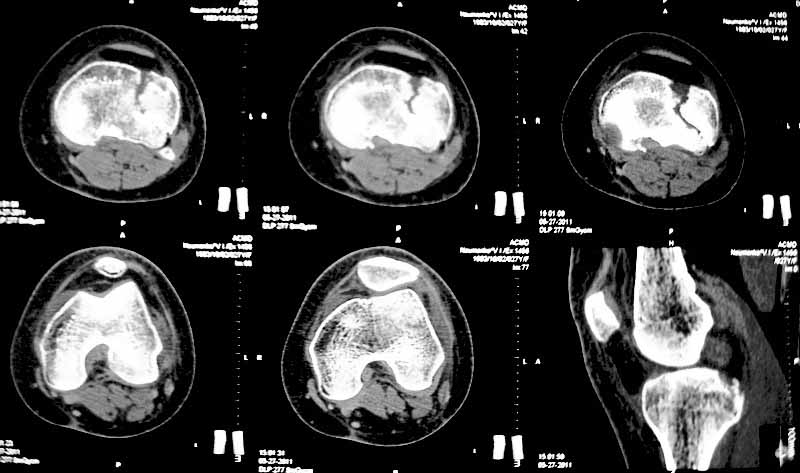

Уважаемые коллеги. Хочу представить вам клинический случай и получить информацию в отношении тактики лечения данной пациентки. Возраст 27 лет, парапланеристка, получила травму в Индии 28 апреля 2011г, упала с мотоцикла, получила боковой удар по левому коленному суставу. Первая помощь оказана в индийской клинике, установлен диагноз - Ссадины левого локтевого сустава, левого плеча, левой и правой стоп, повреждение связок левого коленного сустава (не указано каких). Со слов пациентки выполнены рентгеновские снимки голени (их не отдали). Наложена циркулярная рассеченная скотч-каст повязка без захвата стопы на левую ногу, рекомендовано консервативное лечение со сроком иммобилизации 6 недель. Пострадавшая оставалась в Индии и вернулась 17 мая.

26 мая обратилась ко мне за консультацией с вопросом – можно ли снять иммобилизацию немного раньше и начать ходить без костылей?. СКТ – снимки прилагаю.

-клинически – вальгизация коленного сустава, умеренная сглаженность контуров сустава, постиммобилизационная контрактура сустава, медиальной и латеральной нестабильности сустава нет.

Интересуют вопросы: -тактика лечения: -если операция, то стандартная открытая репозиция с приподнятием мениска, обзором части сустава, подъемом импактированного фрагмента, костной пластикой и фиксацией блокированной пластиной и винтами ( в больнице ЭОПа нет) или есть другие варианты? -понимаю, что операция сложна, идеала достичь будет также сложно, но возможно ли за сустав побороться именно сейчас?, а не ждать ЛФК, реабилитации, получения результатов консервативного лечения и дальнейших артроскопий, остеотомий и пр. -какие результаты лечения можно предположительно получить после выполнения операции с улучшенным, но неидеальным сопоставлением отломков и какие результаты можно ожидать от консервативной методики, будет ли лучше? -если тактика лечения консервативная, то какие ориентировочные сроки осевой нагрузки на больную ногу, сроки перехода на трость. Буду рад выслушать все предложения. Заранее благодарен. С уважением Голиков Валерий, БСМП, Киев